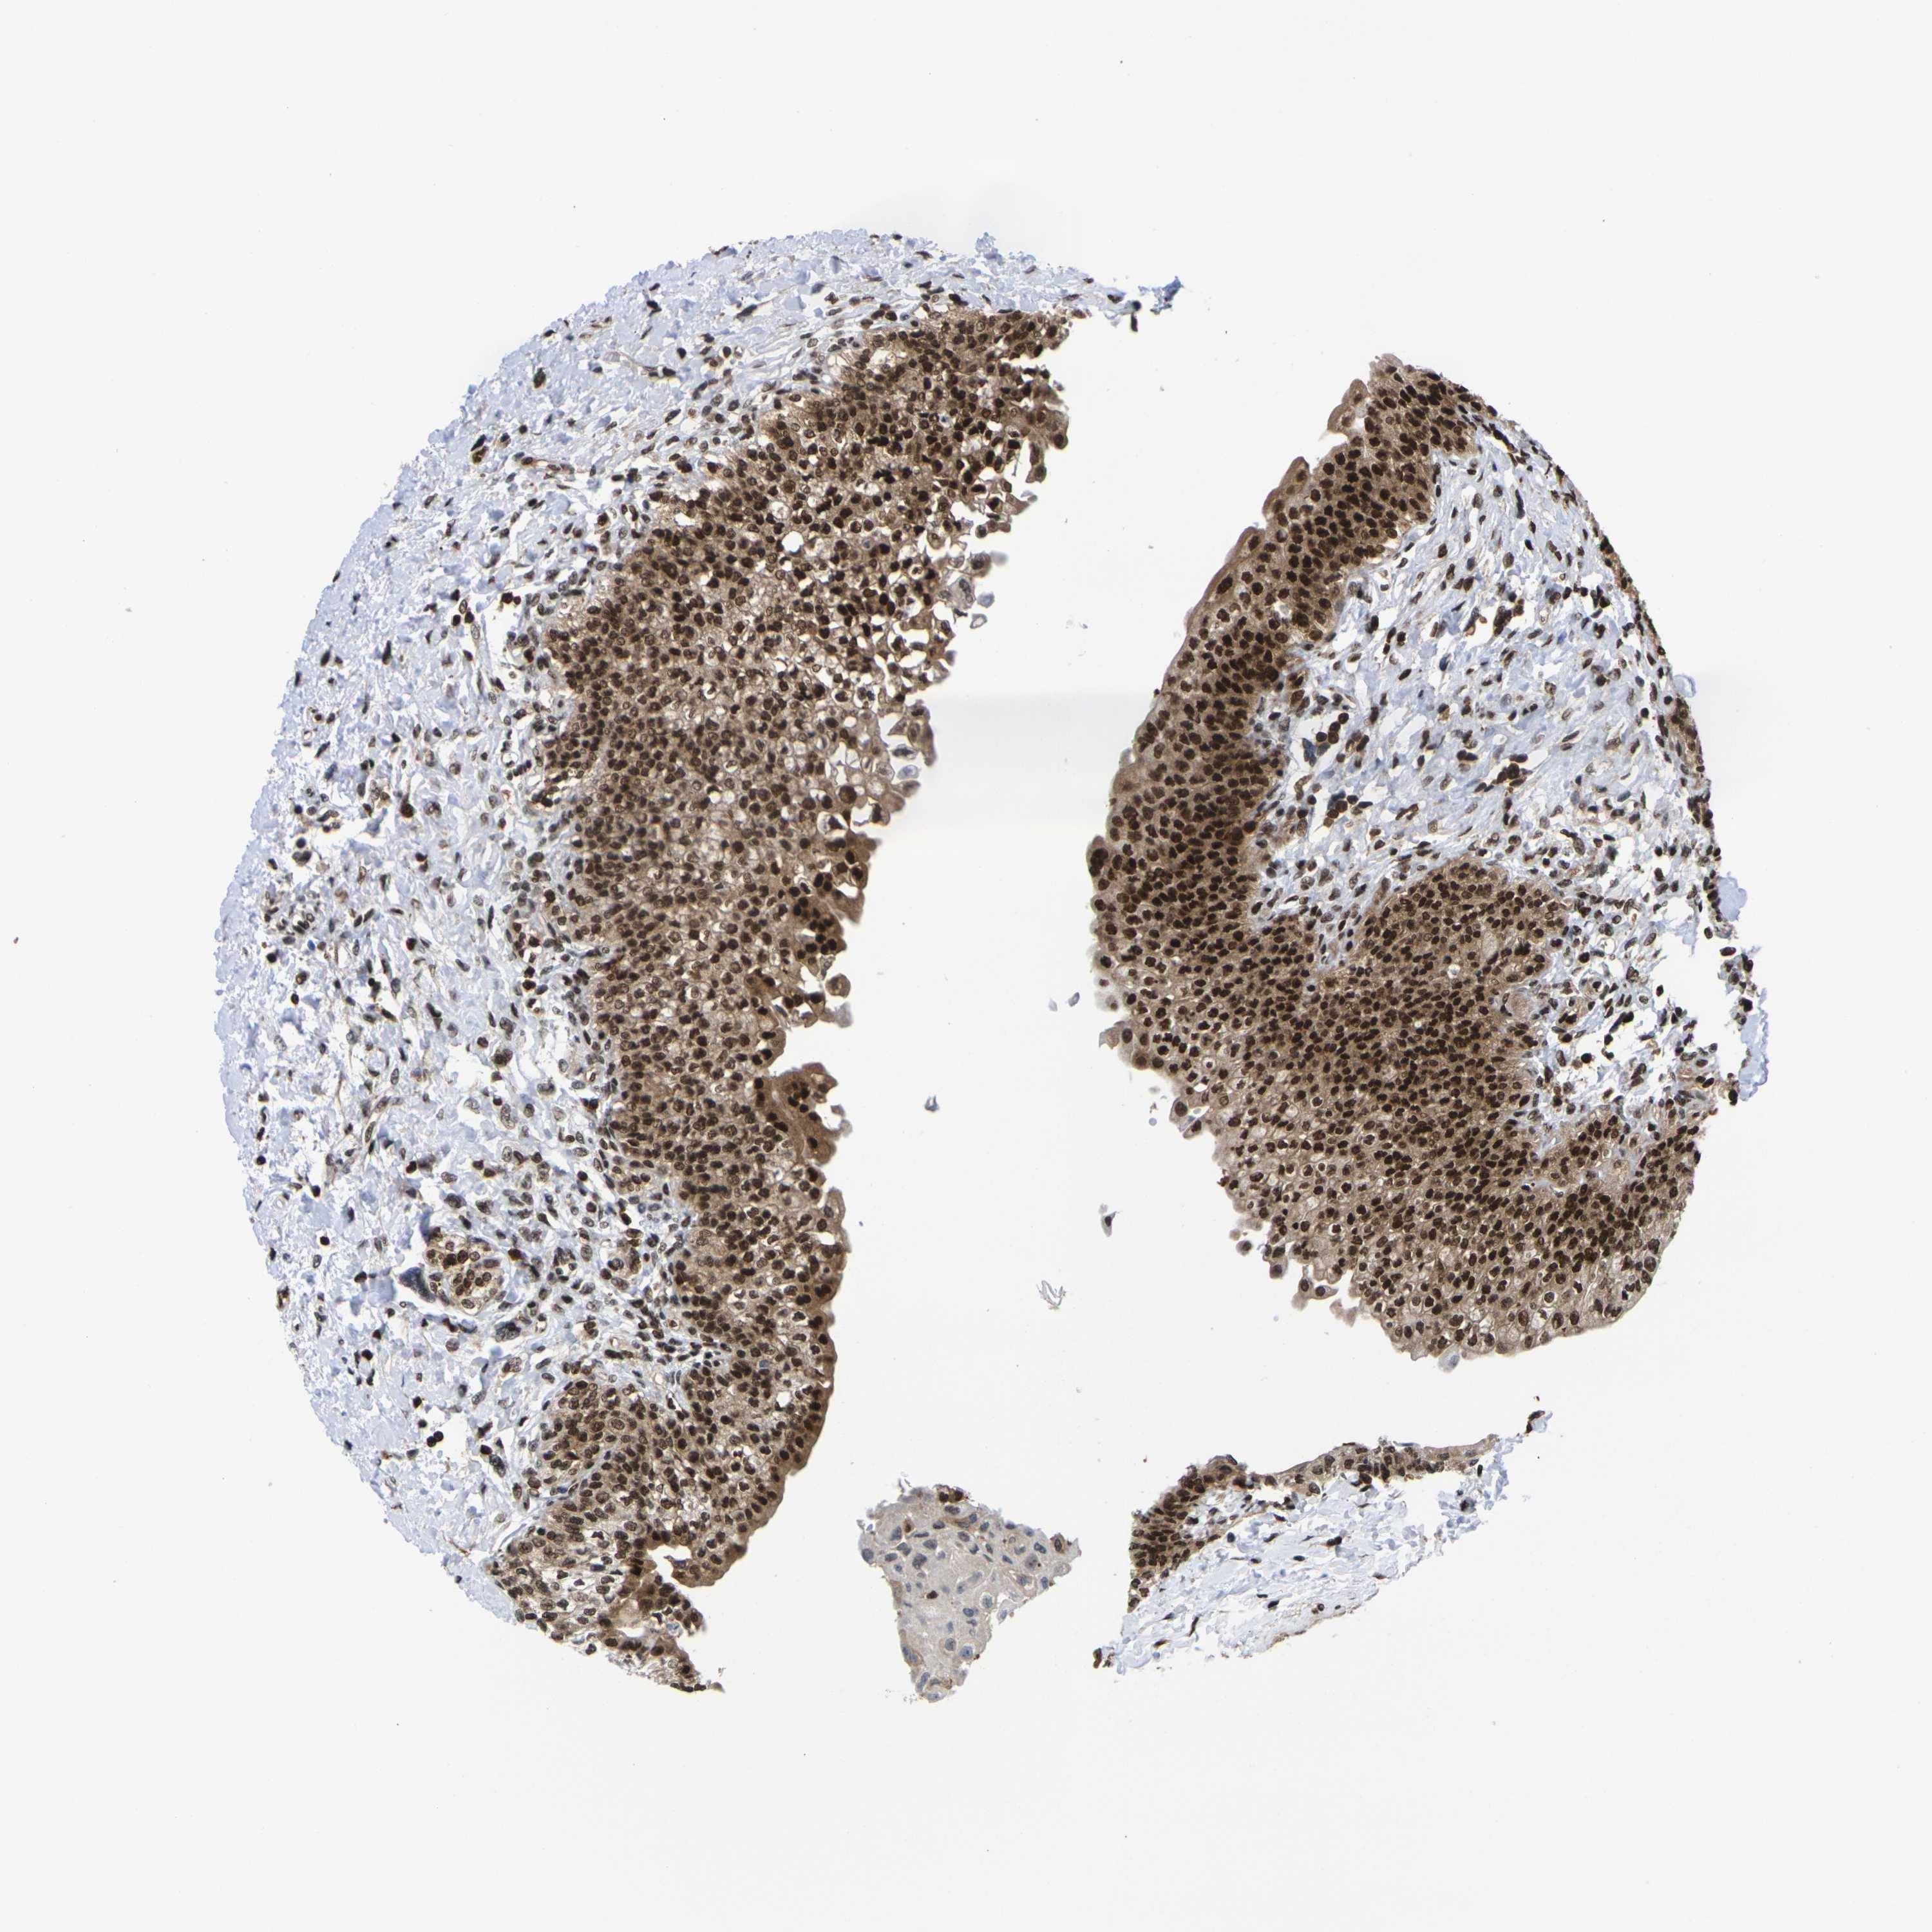

Antibody staining in the annotated cell types in the current human tissue is reported as not detected, low, medium, or high. This score is based on the staining intensity and fraction of stained cells.